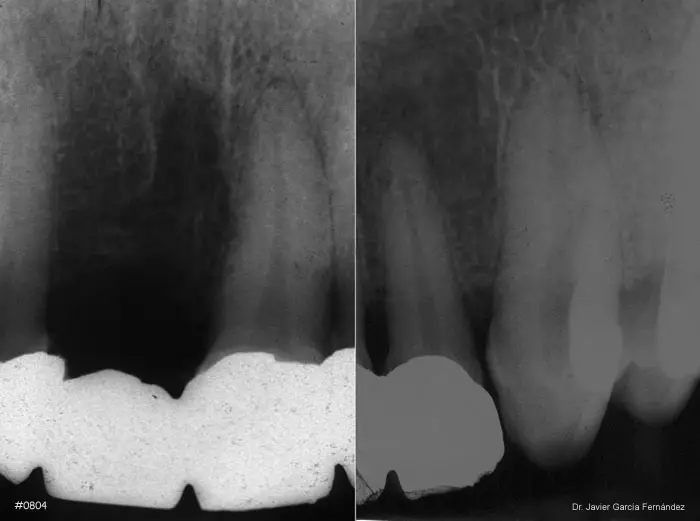

Atlas of Surgical Techniques in Periodontics. Chapter III. Atlas de Técnicas Quirúrgicas en Periodoncia